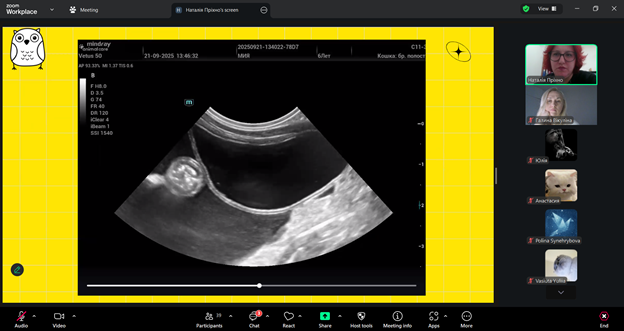

Лектор – Наталія ПРІХНО, яка є кардіологом, лікарем з УЗД даної ветеринарної клініки, розповіла про те, як правильно працювати з УЗД-апаратом, на що звертати увагу під час обстеження котів і собак та які «підводні камені» можуть чекати під час інтерпретації зображень. Було багато корисних порад і реальних випадків з практики — саме те, що найбільше цінують слухачі. Пані Наталія детально пояснила принципи проведення AFAST/TFAST, ключові орієнтири обстеження та їхнє значення у клінічній практиці. Учасники мали змогу ознайомитися з типовими патологіями, які можуть бути виявлені за допомогою цих протоколів, а також з поширеними діагностичними помилками та способами їх уникнення. Окрему увагу було приділено практичним клінічним випадкам, що продемонстрували ефективність AFAST/TFAST у швидкій оцінці стану тварини, прийнятті рішень у невідкладних ситуаціях та моніторингу динаміки стану пацієнта.